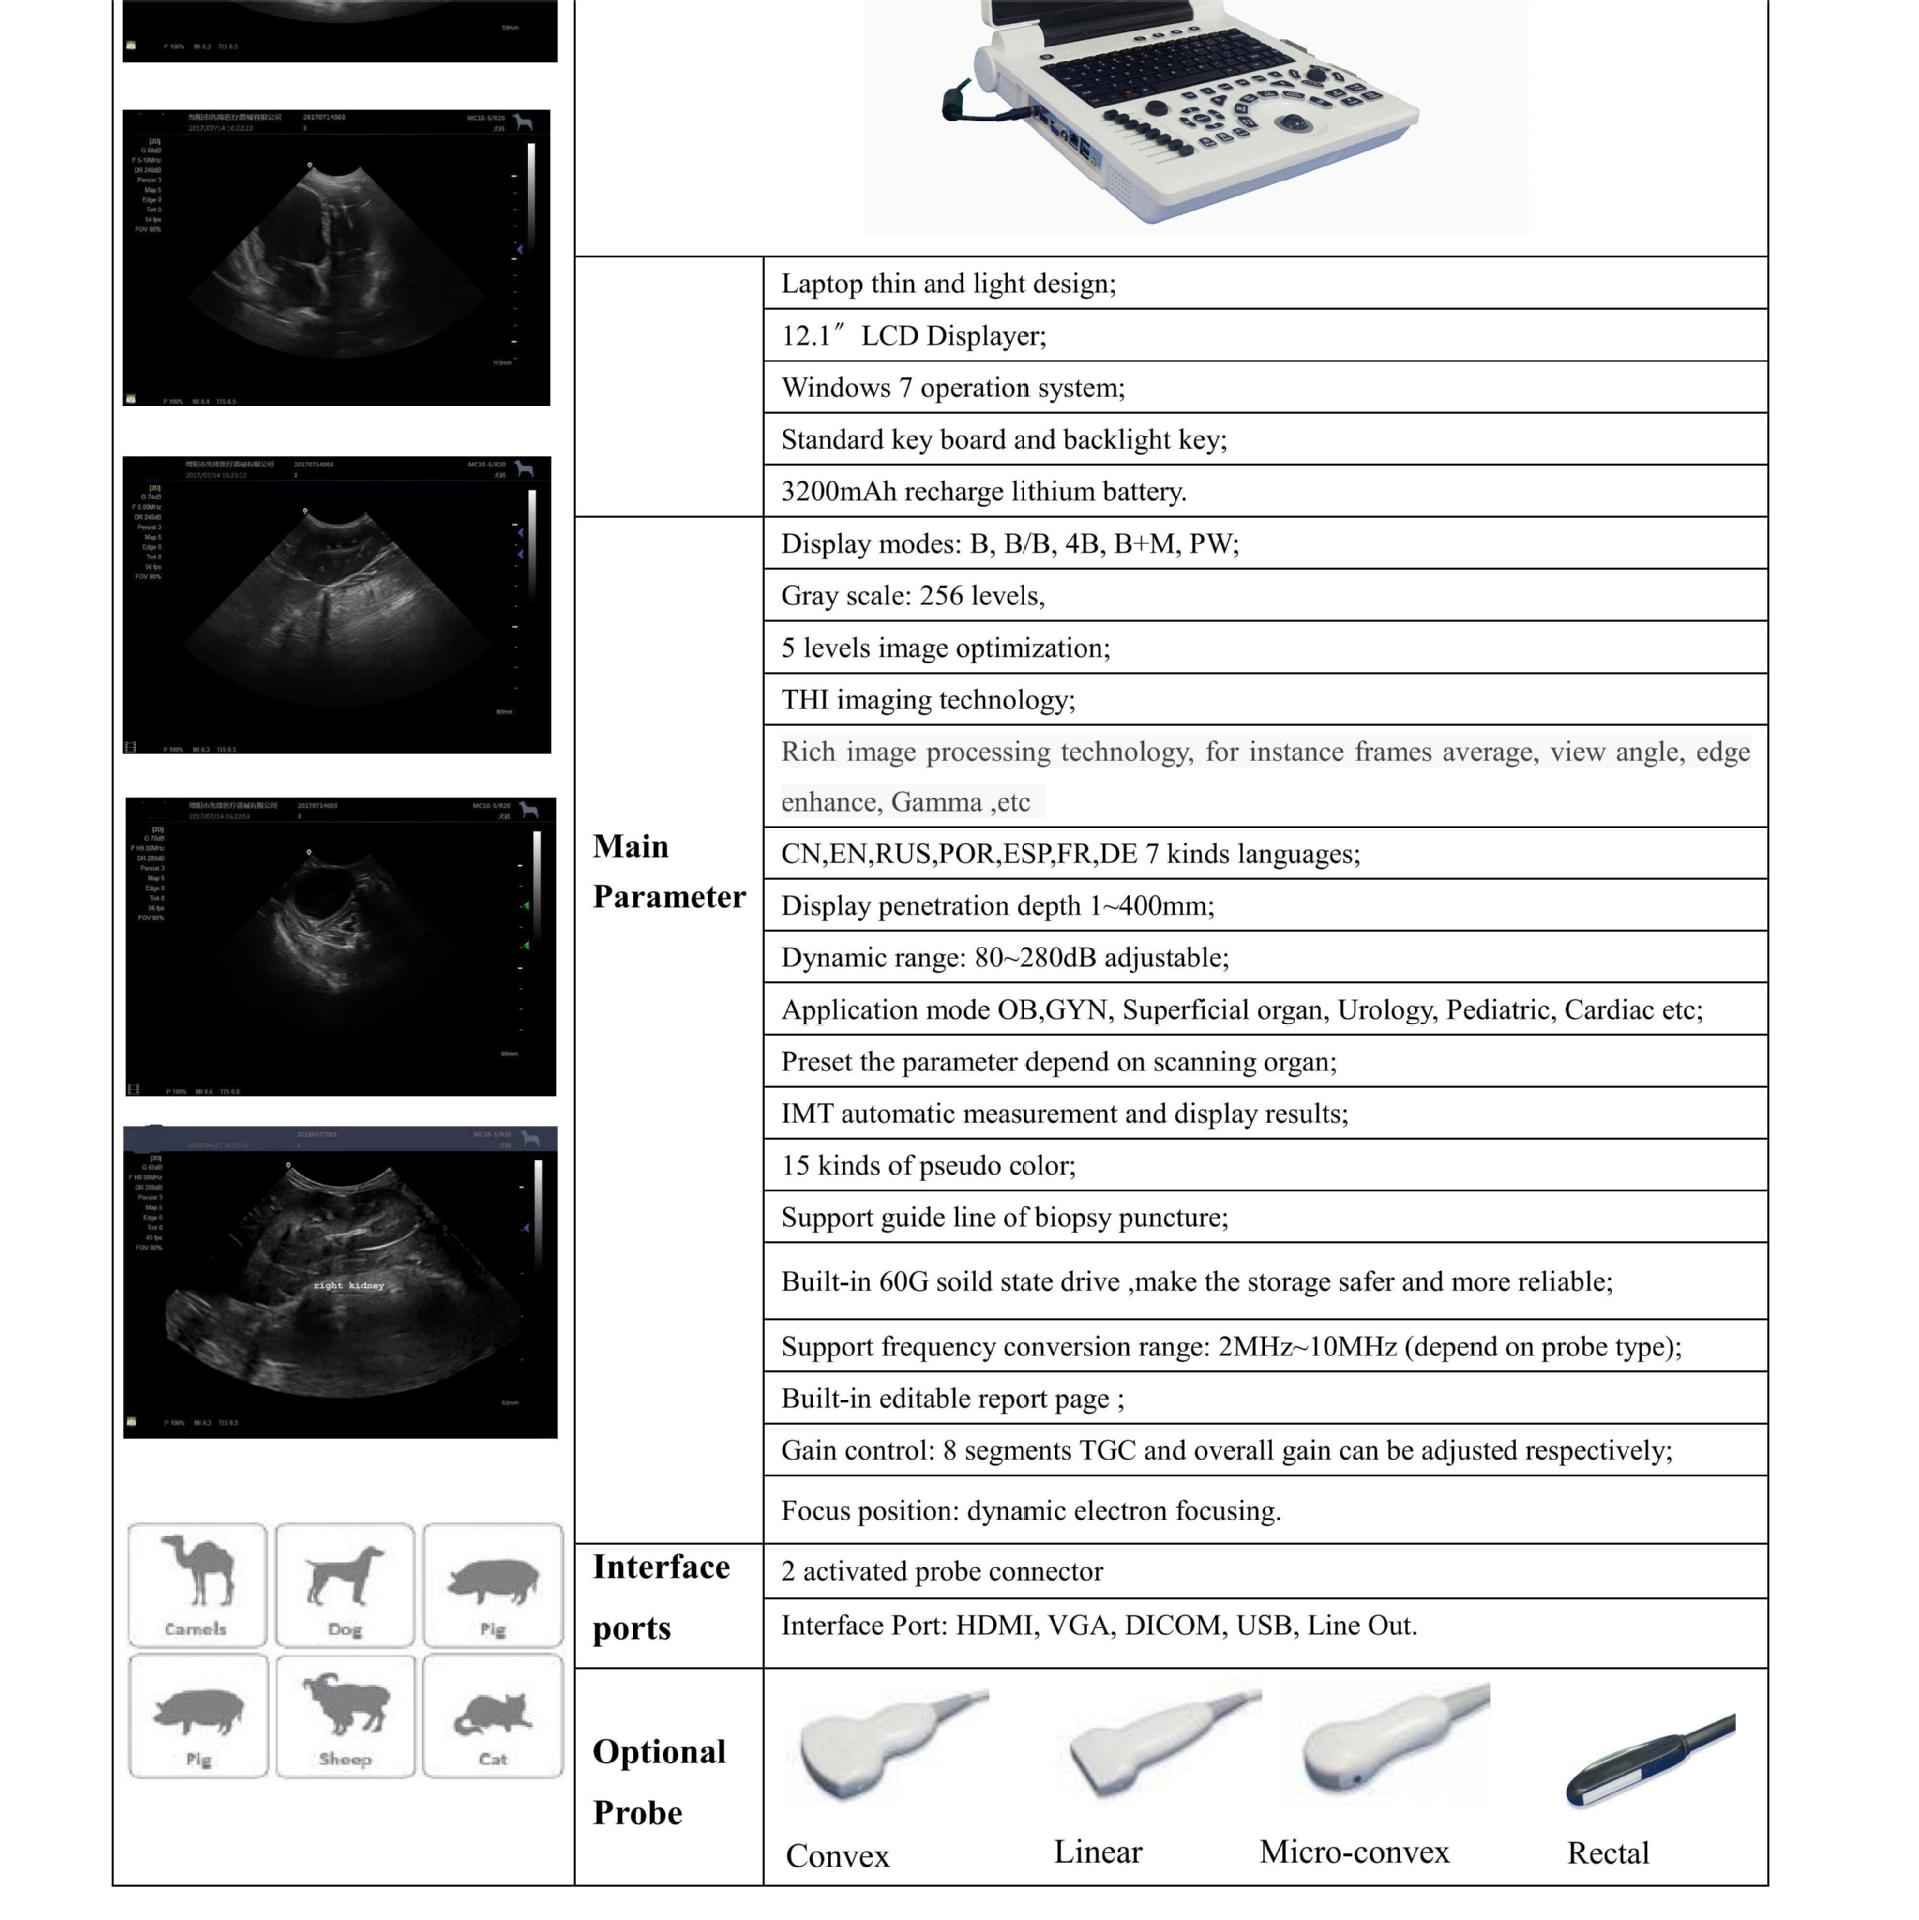

Портативный ультразвуковой аппарат Animal B; Выпуклый массивный зонд; Линейный зонд; Слегка выпуклый зонд; ректальный зонд